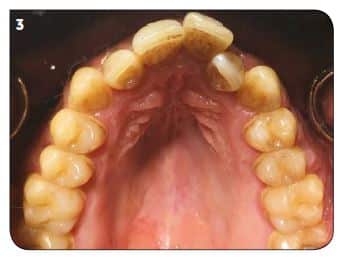

Un patient de 30 ans vient au cabinet pour un encombrement de sa zone antérieure tant maxillaire que mandibulaire. À l’examen clinique, hormis sa DDM, il était en classe 1 molaire des deux côtés, facilitant la prise de décision dans son plan de traitement (Fig.1 à 4).

Suites aux examens, nous avons réalisé un premier ClinCheck permettant d’avoir un premier repositionnement (Fig.5). On peut ici constater :

– une série de 17 aligneurs,

– une série de réductions inter-proximales maxillaires (RIP) pour un total de 1,0 mm réparties entre les 15 et 25,

– une série de réductions inter-proximales mandibulaires (RIP) pour un total de 0,8 mm réparties entre les 15 et 25,

–des taquets répartis sur toutes les dents maxillaires pour optimiser les mouvements voulus,

– des taquets sur quelques dents maxillaires.

La durée du traitement est de 34 semaines avec un changement des aligneurs toutes les 2 semaines (Fig.5 à 7).